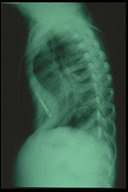

Three days after intercostal drainage of bilateral chylothorax. Both lungs expanded well. Generalized edema was still noted from the film.

Ten days after intercostal drainage of bilateral chylothorax. The baby could breathe without any assistant. Both lungs expanded well and less edema was noted.